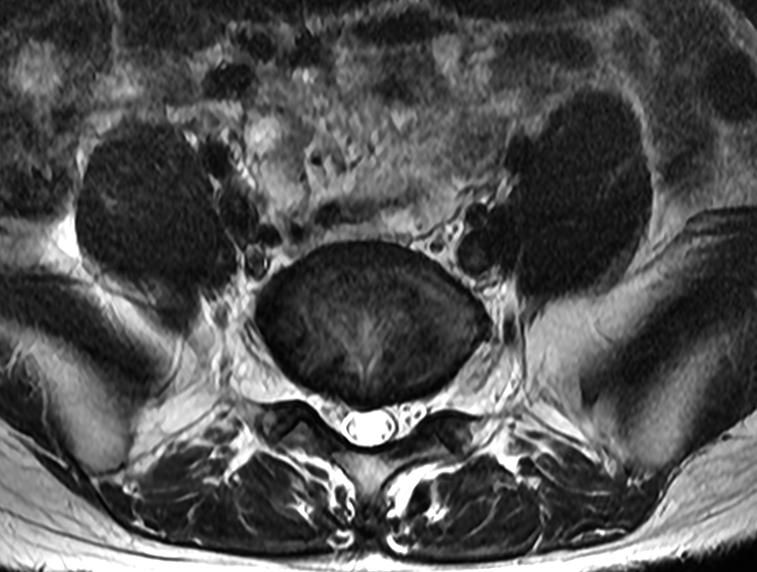

요추 mri 5ㅡ1 디스크입니다.

• 1번 째 사진

• 2번 째 사진